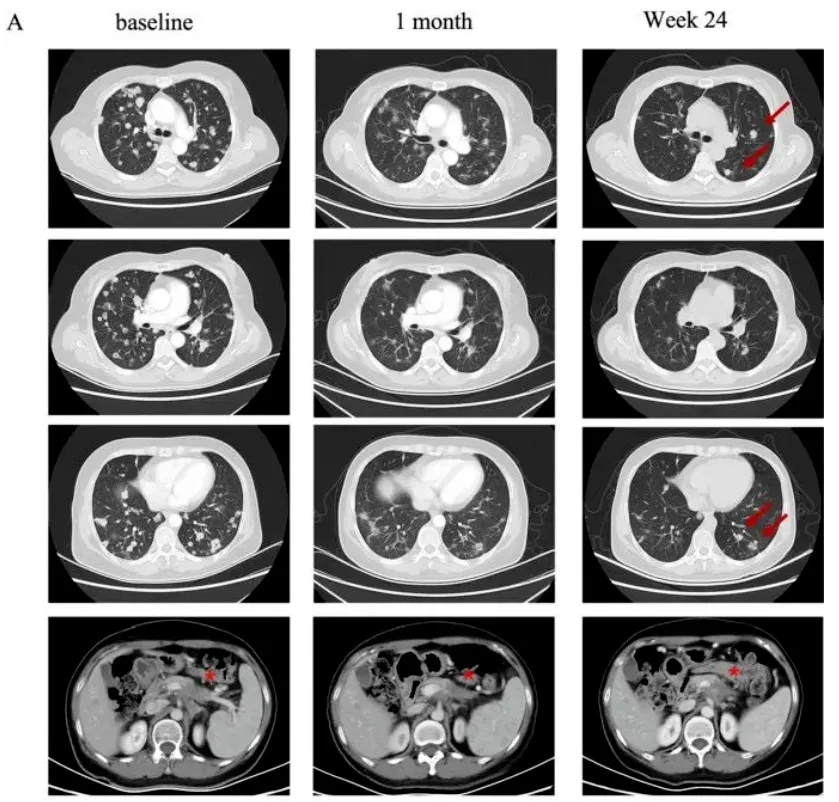

该患者为58岁女性,既往接受标准治疗失败,肿瘤持续进展,已发生全身转移。万念俱灰下,她入组接受了CT041细胞回输治疗。这是一款针对CLDN18.2(即Claudin18.2,在胰腺癌中高表达)的新型CAR-T细胞产品,既往在治疗消化系统恶性肿瘤中获得了良好的缓解率。该患者在CT041治疗后,幸运的达到部分缓解(PR),靶病灶显著缩小30%以上,同时肺转移也出现了大幅缩小(详见下图)!

图 患者治疗前后肺部影像学评估

▲图源“BMC”,版权归原作者所有,如无意中侵犯了知识产权,请联系我们删除

注;“★”表示“原发病变”。